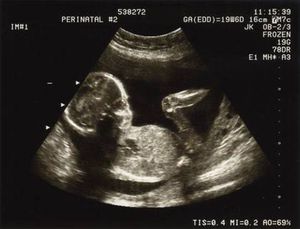

The perinatal period commences at 22 completed weeks (154 days) of gestation and ends seven completed days after birth. Perinatal and maternal health are closely linked.Perinatal mortality refers to the number of stillbirths and deaths in the first week of life (early neonatal mortality).